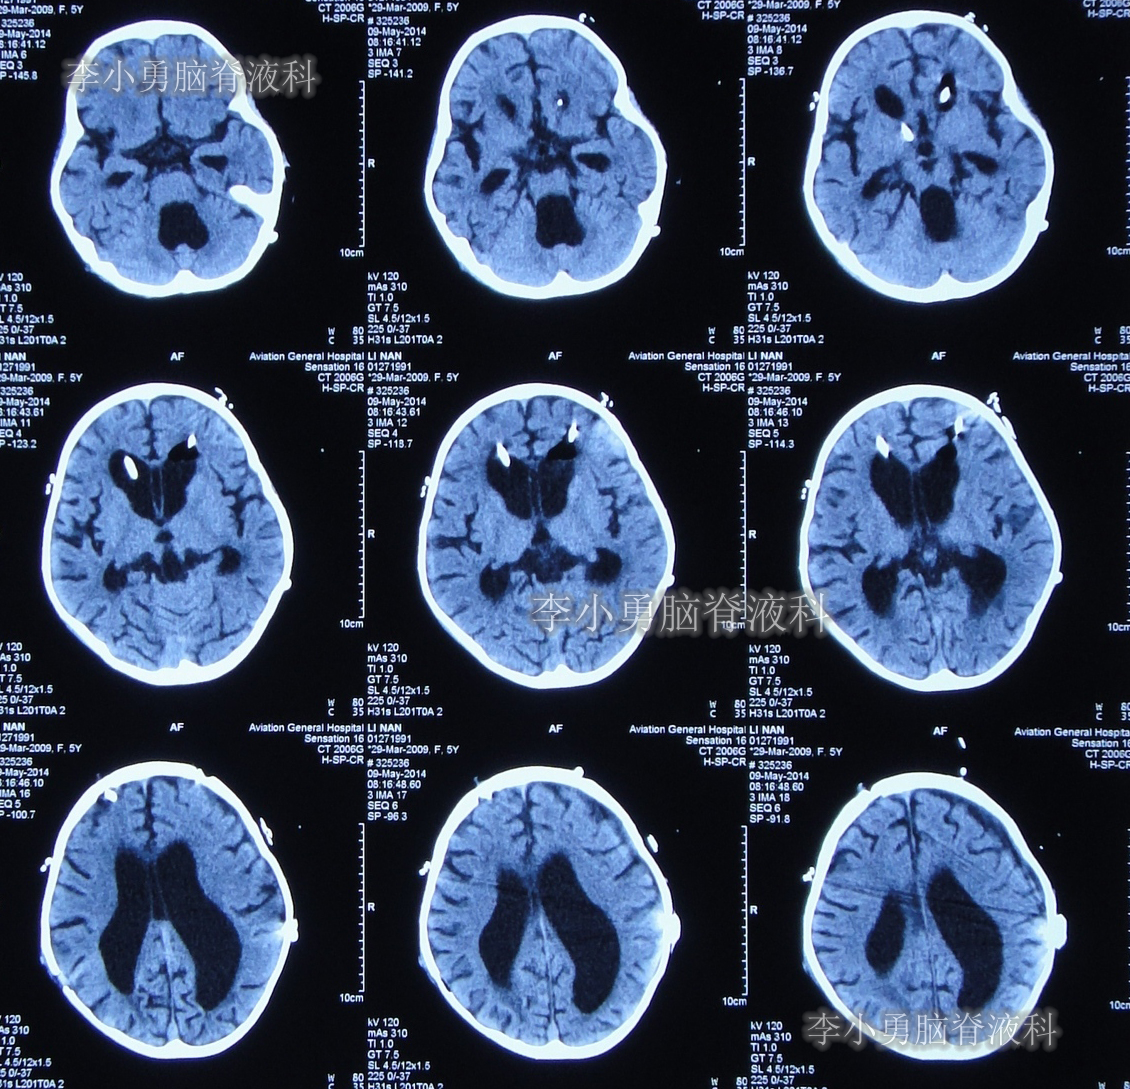

数天之后即在2013年9月2日,为治疗脑积水,患儿至河南省郑州市某三甲医院神经外科就诊,当日头颅CT示严重脑积水并第四脑室扩张严重(图-1);当天收入院。在住院后次日即2013年9月3日,进行了右侧额角脑室腹腔分流术。

图-1:2013年9月2 日头颅CT

于2014年2月11日即脑室心房分流术后第122天时,患儿突然再次出现头痛和呕吐的症状,立即又第3次返回河南省郑州市某三甲医院神经外科住院治疗,当天查头颅CT显示脑室系统再度扩张严重(图-2)。

图-2:2014年2月11日头颅CT

第3次住院后第10天即2014年2月21日,复查头颅CT显示脑室系统仍扩张严重(图-3)。

图-3:2014年2月21日头颅CT